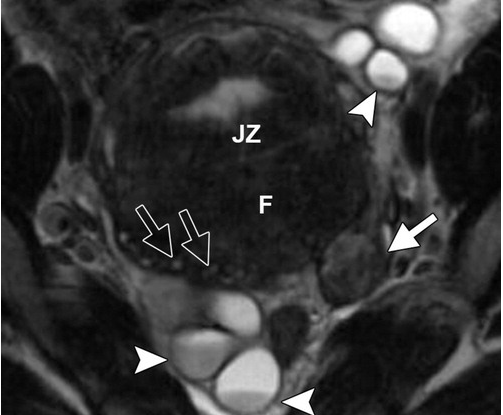

Stage of this endometrial carcinoma with no other abdominal or pelvic findings.

What is stage IB?

T2 image shows intermediate to high intensity lesion endometrial tumor. DWI/ADC shows restricted diffusion extending to >50% of the myometrium.